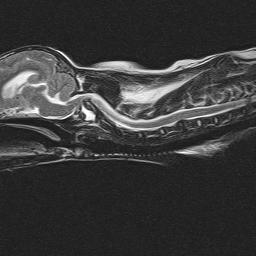

aalux-mrsagt2

Atlanto-axial (AA) subluxation